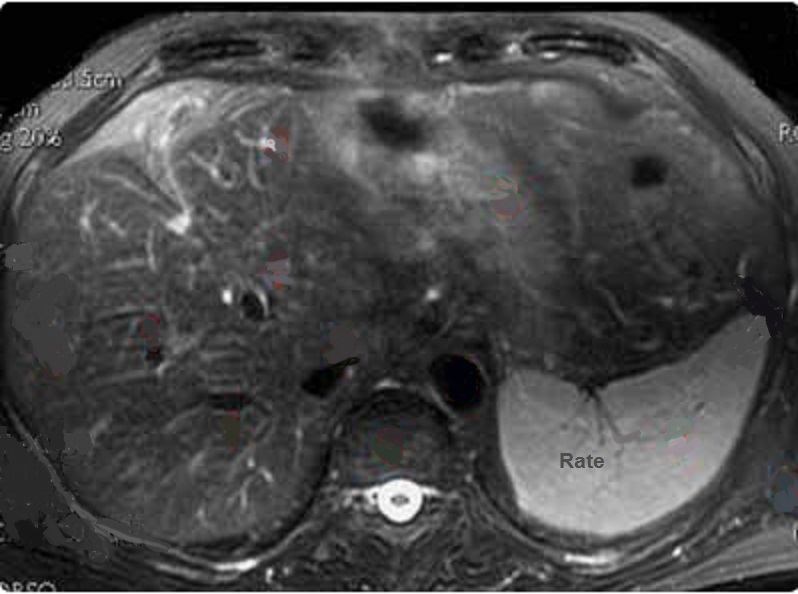

Image

radiologique IRM ponderee T1 de la rate avec aspect

parenchymateuse homogene et leregemant moins

intensite que le foie |

Aspect radiologique IRM de

la rate pondere sur T2 FatSat . La parenchyme de la

rate est homogène et tres hypersignal que le foie et

les autres organes . Image IRM T2 FATSAT coupe axial |

Aspect de la rate au temps de evacuation

apres injection de chelate de Gadolinium . Le

parenchyme de la rate est homogene et isosignal par

rapport au foie |